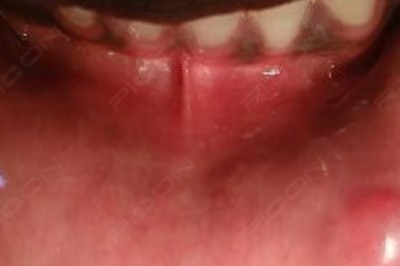

Tag: Fibroma

Excision of Fibroma using Dental Soft-tissue Diode Laser

An advantage of diode laser application compared to scalpel use is the provision of a relatively bloodless surgical incision with minimal swelling and scarring postoperatively.